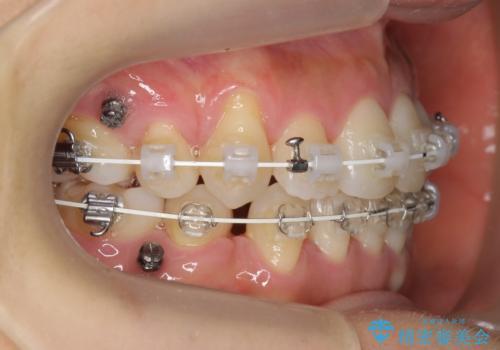

- ワイヤー矯正

- 3年

- 10-30回

小臼歯抜歯を行い、ワイヤー矯正を行いました。

時間はかかりましたがしっかり治療することができました。